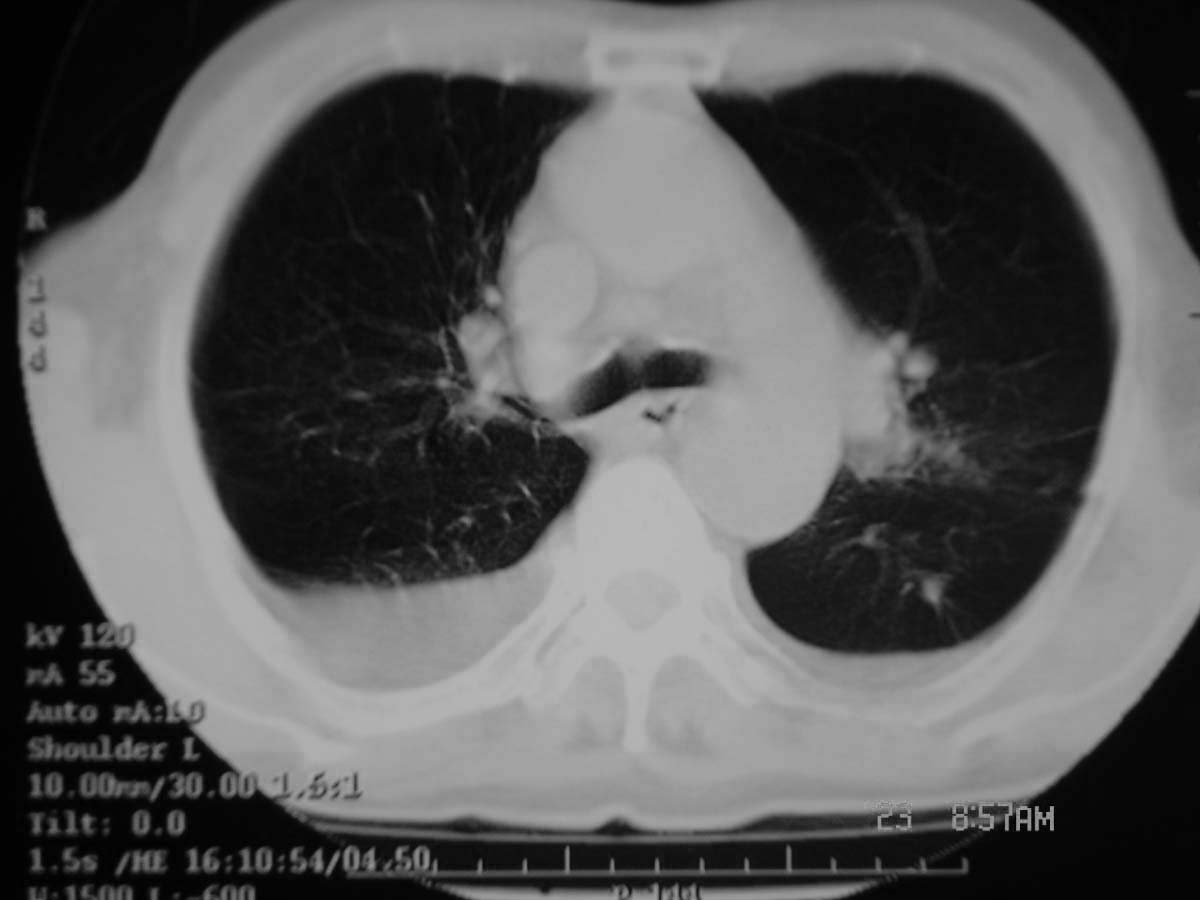

以下是引用守望可可西里在2006-11-23 14:33:00的发言:[br][br] 糖尿病病人很容易继发结核,病人又有双侧胸膜增厚、粘连、胸腔积液以及双上肺的斑片状、条索状影结核病灶影,以一元论考虑,右下肺病变首先考虑干酪性肺炎,可以正规抗炎治疗后复查,排除一般的肺炎。